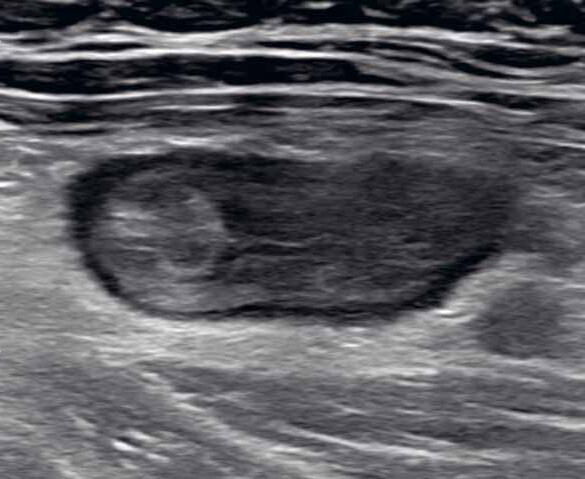

2.2 Ultrazvuk

Ultrazvukové vyšetření tenkého střeva je dnes široce využívané v diagnostice postižení trávicí trubice. Uplatňuje se především u pacientů s Crohnovou nemocí, ale také u pacientů s dalšími enteropatiemi.

Sonograficky můžeme hodnotit šířku a echogenitu střevní stěny, postižení jejích jednotlivých vrstev, patologické změny v okolí střeva a komplikace (absces, pseudotumor, píštěle, konvolut kliček apod.). Sledování dynamiky onemocnění a opakované kontroly přitom pacienta nepoškozují radiační zátěží, proto je vyšetření výhodné zvláště pro děti a adolescenty. Pacient nemusí být nijak speciálně připravován, nemusí být lačný a vyšetření lze libovolně opakovat.

Technika ultrazvukového vyšetření střev zahrnuje použití dvou různých sond: nízkofrekvenční konvexní sondy (3–5 MHz) a vysokofrekvenční lineární sondy (5–17 MHz). Nemocné vyšetřujeme v poloze na zádech nejprve pomocí nízkofrekvenční konvexní sondy, abychom vizualizovali hlouběji uložené struktury a detekovali výraznější patologie, jako například signifikantní ztluštění střevní stěny, dilataci střevních kliček, přítomnost markantních fistulací nebo abscesů. Vyšetření nízkofrekvenční konvexní sondou je vhodné také u obézních pacientů, u nichž vyšetření vysokofrekvenční lineární sondou nemusí být výtěžné. Po vstupním vyšetření břicha nízkofrekvenční sondou přistupujeme k vyšetření pomocí vysokofrekvenční lineární sondy, která nám umožní detailnější vizualizaci jednotlivých vrstev střevní stěny

Mukóza se zobrazuje jako hypoechogenní, submukóza jako hyperechogenní, svalovina je hypoechogenní a seróza hyperechogenní. Lumen střeva většinou obsahuje vzduch, který při ultrazvukovém vyšetření vytváří hyperechogenní odraz s akustickým stínem. Jednotlivé vrstvy střevní stěny a vzduch v lumen jsou dobře viditelné i u zdravých jedinců. Normální šíře stěny se pohybuje v rozmezí 2–3 mm.

Obr. 1–3: CEUS. Pacient s Crohnovou nemocí ve fázi aktivního zánětu. Po podání kontrastní látky je patrné postupné sycení střevní stěny (1, 2, levá část obrázku), která je výrazně zesílená s akcentovanou hypoechogenní sliznicí (1, 2, pravá část obrázku). Křivka sycení pak svědčí rovněž pro akutní fázi zánětu (3).